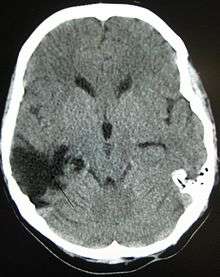

One type of focal injury, cerebral laceration, occurs when the tissue is cut or torn.[30] Such tearing is common in orbitofrontal cortex in particular, because of bony protrusions on the interior skull ridge above the eyes.[24] In a similar injury, cerebral contusion (bruising of brain tissue), blood is mixed among tissue.[15] In contrast, intracranial hemorrhage involves bleeding that is not mixed with tissue.[30]

Hematomas, also focal lesions, are collections of blood in or around the brain that can result from hemorrhage.[3] Intracerebral hemorrhage, with bleeding in the brain tissue itself, is an intra-axial lesion. Extra-axial lesions include epidural hematoma, subdural hematoma, subarachnoid hemorrhage, and intraventricular hemorrhage.[31] Epidural hematoma involves bleeding into the area between the skull and the dura mater, the outermost of the three membranes surrounding the brain.[3] In subdural hematoma, bleeding occurs between the dura and the arachnoid mater.[15] Subarachnoid hemorrhage involves bleeding into the space between the arachnoid membrane and the pia mater.[15] Intraventricular hemorrhage occurs when there is bleeding in the ventricles.[31]

Surgery can be performed on mass lesions or to eliminate objects that have penetrated the brain. Mass lesions such as contusions or hematomas causing a significant mass effect (shift of intracranial structures) are considered emergencies and are removed surgically.[15] For intracranial hematomas, the collected blood may be removed using suction or forceps or it may be floated off with water.[15] Surgeons look for hemorrhaging blood vessels and seek to control bleeding.[15] In penetrating brain injury, damaged tissue is surgically debrided, and craniotomy may be needed.[15] Craniotomy, in which part of the skull is removed, may be needed to remove pieces of fractured skull or objects embedded in the brain.[99] Decompressive craniectomy (DC) is performed routinely in the very short period following TBI during operations to treat hematomas; part of the skull is removed temporarily (primary DC).[100] DC performed hours or days after TBI in order to control high intracranial pressures (secondary DC) has not been shown to improve outcome in some trials and may be associated with severe side-effects.[2][100]